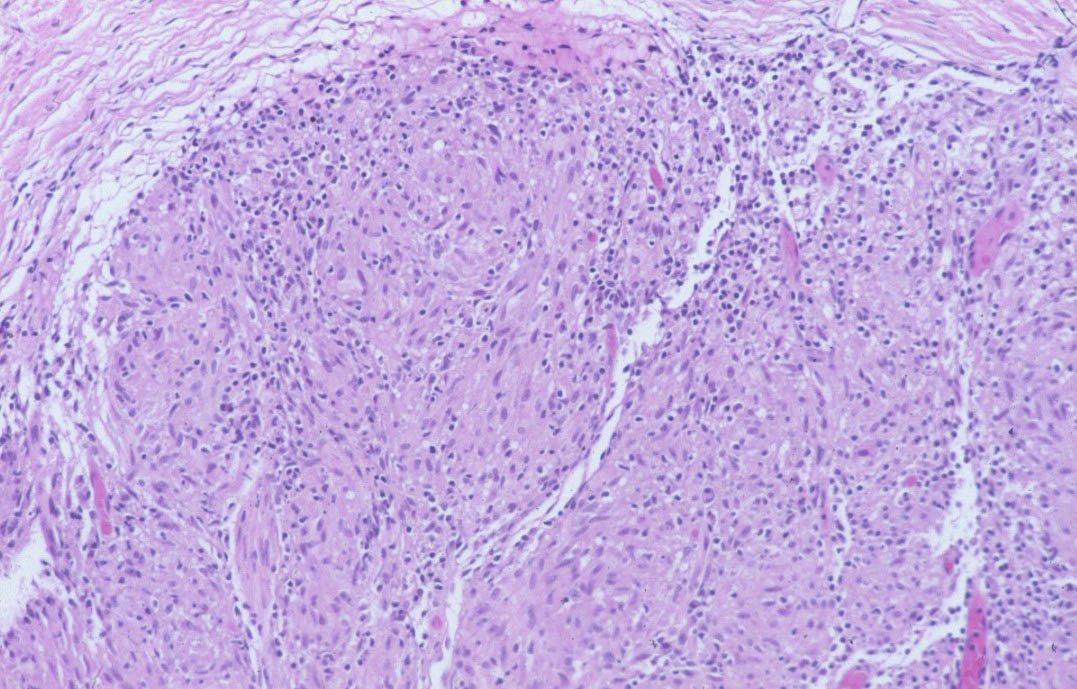

Differential DiagnosisThe histologic differentiation of sarcoidosis from lupus vulgaris may be very difficult, and it is

occasionally impossible. There is no absolute histologic criterion by which the two diseases can be differentiated with certainty. However, as a rule, the infiltrate in sarcoidosis lies scattered throughout the dermis, whereas the infiltrate in lupus vulgaris is located close to the epidermis. Furthermore, sarcoidosis usually shows few lymphoid cells at the periphery of the granulomas, giving them the appearance of “naked” granulomas. By contrast, lupus vulgaris often shows a marked inflammatory reaction around and between the granulomas. The granulomas of sarcoidosis usually show much less central necrosis than the granulomas of lupus vulgaris ; however, not all biopsies of tuberculosis show necrosis, and some biopsies of sarcoid do. The epidermis in sarcoidosis is usually normal or atrophic. In lupus vulgaris, in addition to atrophy, areas of ulceration, acanthosis, and pseudocarcinomatous hyperplasia are not uncommon. The absence of identifiable mycobacteria with acid-fast stain cannot be used to exclude tuberculosis because the organisms in lupus vulgaris are scarce and may be difficult or impossible to find.

Foreign-body granulomas can also resemble sarcoidosis. Polariscopic examination in search of doubly refractile material, such as silica, should be performed on biopsies suspected of being sarcoidosis. The presence of foreign material does not exclude a concurrent diagnosis of sarcoidosis . The papular type of acne rosacea occasionally shows “naked” tubercles indistinguishable from those of sarcoidosis, but unlike sarcoid, they are usually perifollicular.

Tuberculoid leprosy, which may show granulomas in association with only a sparse lymphocytic infiltrate, can also be difficult to distinguish from sarcoidosis. Only 7% of cases of tuberculoid leprosy show acid-fast bacilli, and then only a few, so that they may easily be overlooked . The most likely place to find bacilli is within degenerated dermal nerves (the granulomas of tuberculoid leprosy form around dermal nerves that are undergoing necrosis). The granulomas of tuberculoid leprosy show small areas of central necrosis more often than those of sarcoidosis. In addition, the granulomas of tuberculoid leprosy, in contrast with those of sarcoidosis, follow nerves and therefore often appear elongated . Clinical correlation may be required to distinguish between these two diseases. For example, in the United States, leprosy virtually can be excluded if a patient has not been in an endemic area (either in a foreign country or where it is carried in armadillos domestically, e.g., Texas and Louisiana) or has not had prolonged close contact with another individual with the disease